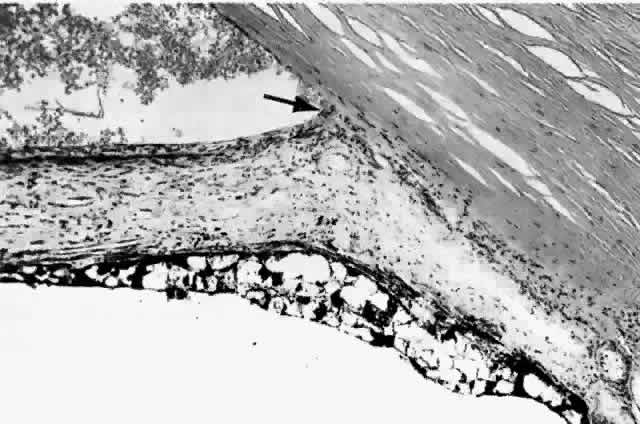

Histologically, new vessels develop between the retinal surface and the posterior surface of the formed vitreous (Fig. 12). With NVE, there is a demonstrable break through the internal limiting membrane (Fig. 13).20 Early-developing new vessels have lumina even at the proliferating tips.53 Active new vessels have endothelial cells and pericytes, with fenestrations. Morphologically, fenestrations are areas ranging from 40 to 80 nm in diameter where the cell membranes are focally fused, and are normal findings in capillaries outside of the retina and brain. They allow increased permeability and are responsible for the diffuse leakage of fluorescein seen from new vessels on angiography. Inactive or “ghost” new vessels are acellular, having lost both endothelium and pericytes.39 With time, fibrous tissue develops and accompanies the new vessels. The vessels themselves may leak and bleed into the vitreous, leading to visual loss.

Fig. 12. Neovascularization at the disc with fibrous proliferation. The fibrovascular membrane overlies the internal limiting membrane, which is wrinkled (arrows). The retinal detachment is artifactual. (PAS, × 19.5)

Fig. 13. Neovascularization away from the disc. The fibrous tissue has contracted, imparting a triangular shape to the membrane. Active new vessels are present throughout. The dark folds are artifactual. (H&E, × 31.25)